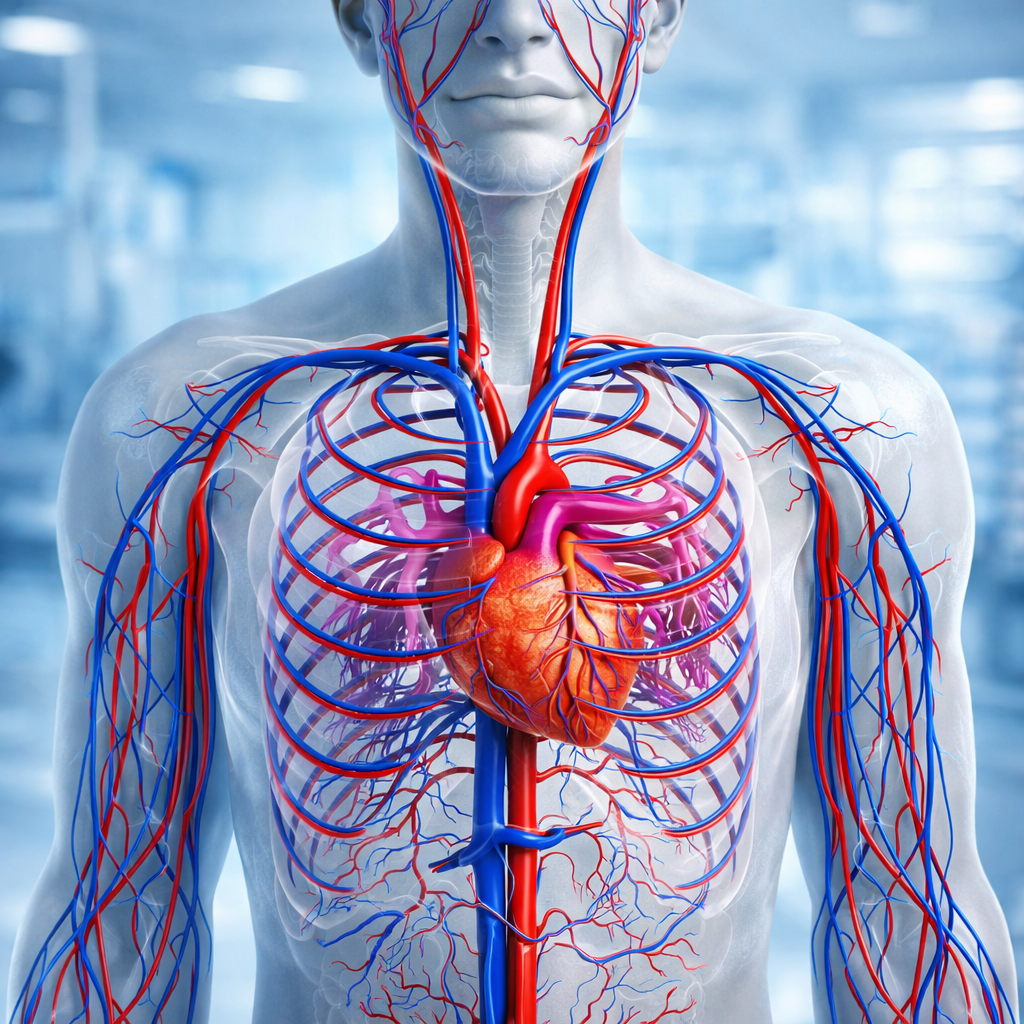

Tratamiento Circulatorio

El tratamiento circulatorio está enfocado en mejorar el flujo sanguíneo y la salud de los vasos sanguíneos, ayudando a prevenir y aliviar molestias asociadas a una circulación deficiente, como dolor, pesadez o hinchazón en las extremidades.

¿En qué consiste?

Incluye una valoración médica personalizada y, según cada caso, el uso de tratamientos médicos, recomendaciones de actividad física, cambios en el estilo de vida y apoyo nutricional para favorecer una mejor circulación.

¿Cuándo se recomienda?

- Sensación de piernas cansadas o pesadas.

- Hinchazón en piernas o tobillos.

- Frialdad o adormecimiento en extremidades.

- Aparición de várices o antecedentes circulatorios.

- Permanecer mucho tiempo sentado o de pie.

Beneficios

- Mejora el flujo sanguíneo.

- Reduce la hinchazón y el malestar.

- Ayuda a prevenir complicaciones circulatorias.

- Aporta bienestar y calidad de vida.

Importante

Todo tratamiento circulatorio debe realizarse bajo supervisión médica, evitando la automedicación y siguiendo las indicaciones profesionales.